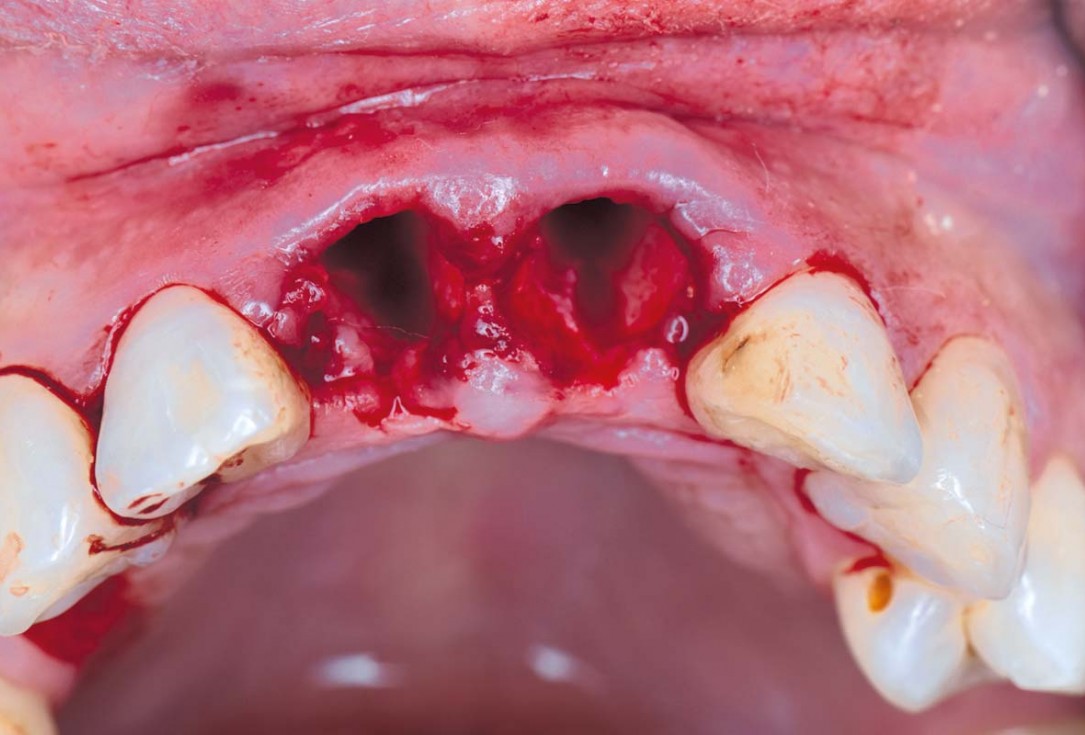

03/22 - Initial clinical situation – Tooth extractioncerabone® and mucoderm® for immediate implantation in the aesthetic area - Dr. D. Robles